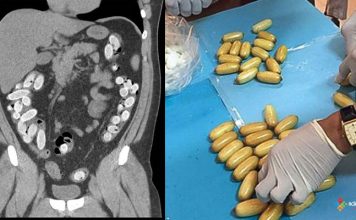

Batın (Abdominal) Travmasına Acil Yaklaşım

Abdominal travmalar, acil servislerde sık karşılaşılan ve hızlı tanı ile etkin yönetim gerektiren önemli travma nedenlerindendir. Travmanın şiddeti; hafif karın ağrısından, masif intraabdominal kanama...